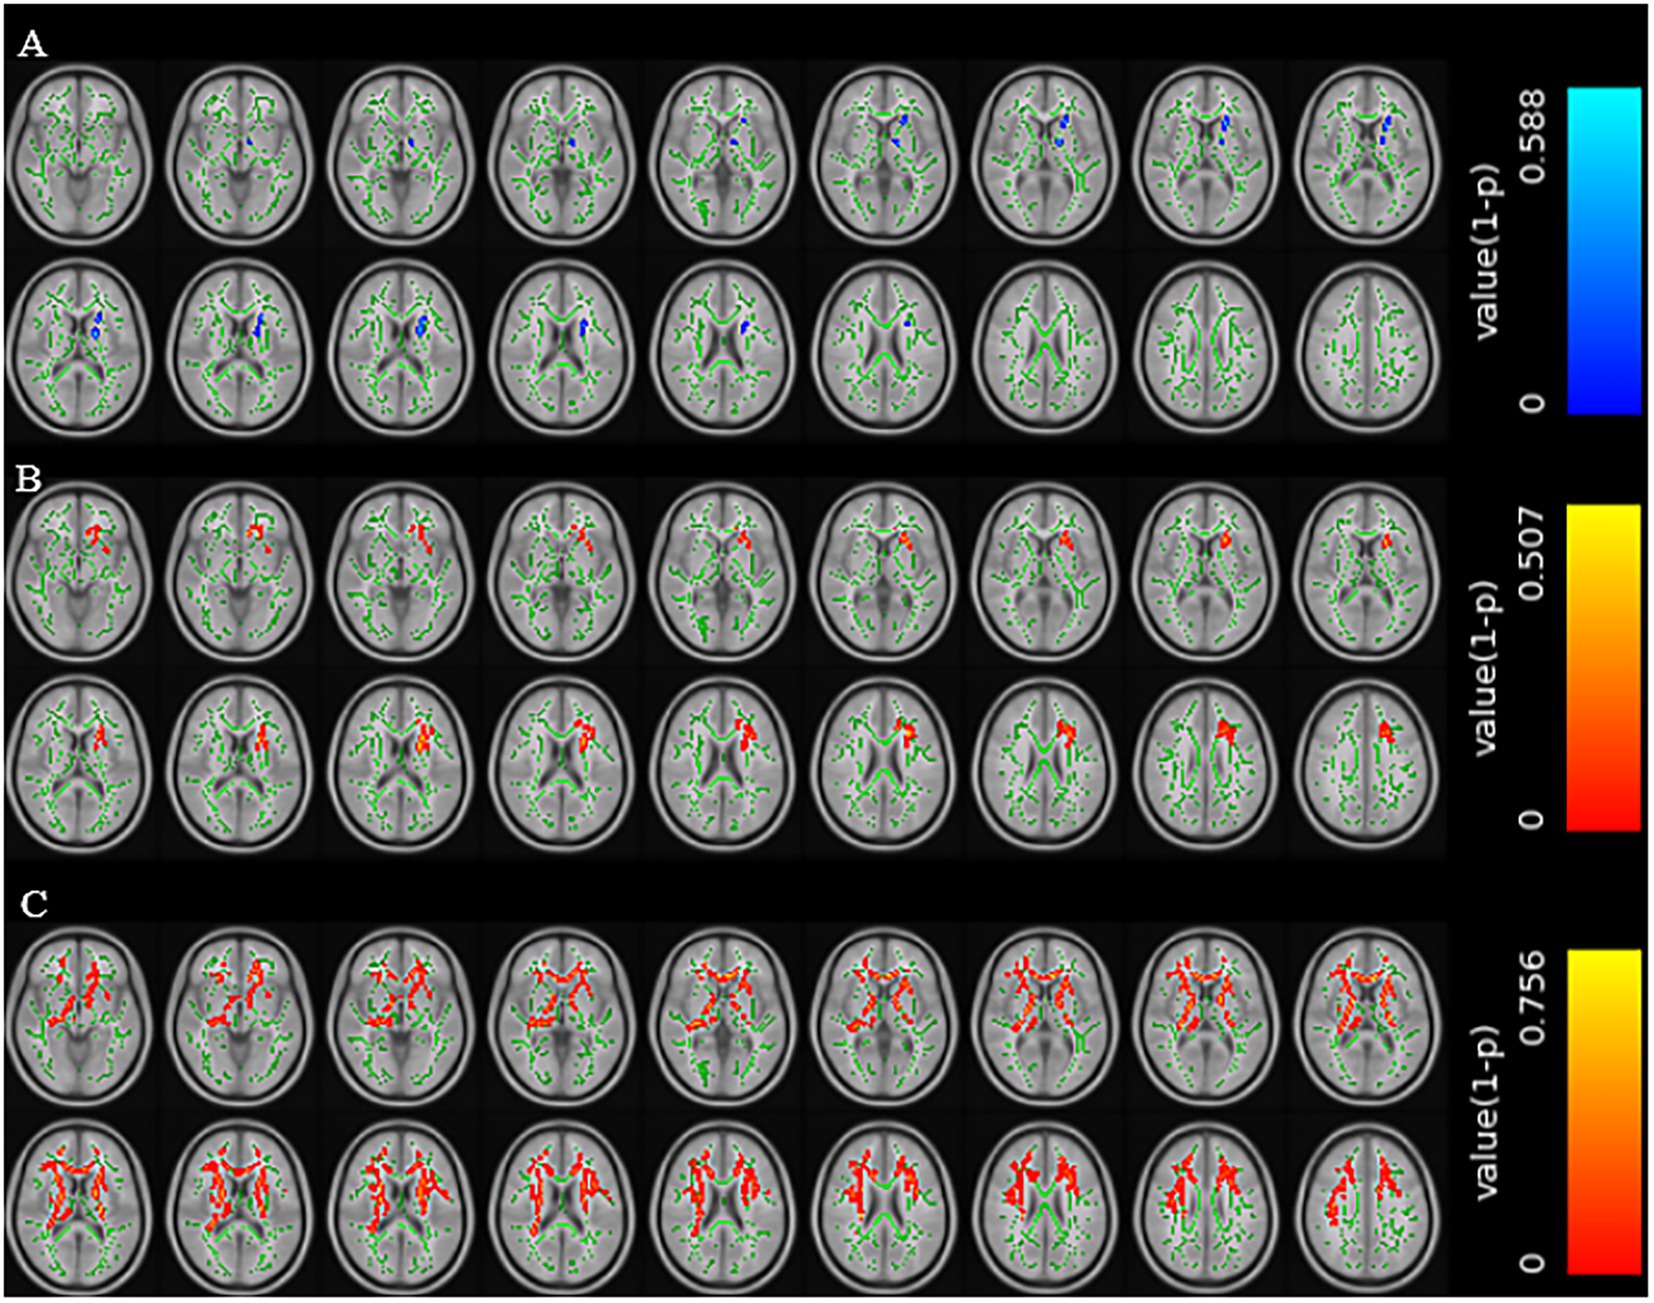

Compared with patients without cognitive impairment, patients with cognitive impairment showed decreased FA values in the left anterior limb of the internal capsule, left posterior limb of the internal capsule, left anterior radiation, and left superior radiation (TFCE corrected, p < 0.01); increased MD values in the genu of the corpus callosum, body of the corpus callosum, left anterior limb of the internal capsule, left anterior radiation, left superior radiation, left external capsule, and left superior fronto-occipital fasciculus (TFCE corrected, p < 0.01); and increased RD values in multiple regions including the genu and body of the corpus callosum, bilateral anterior and posterior limbs of the internal capsule, bilateral superior and anterior radiation, and several other tracts (TFCE corrected, p < 0.01) (Figure 2).

Figure 2. Brain regions with reduced FA values in the CSVD group with cognitive impairment (A). Brain regions with increased MD values in the CSVD group with cognitive impairment (B). Brain regions with increased RD values in the CSVD group with cognitive impairment (C) (TFCE correction, p < 0.01).